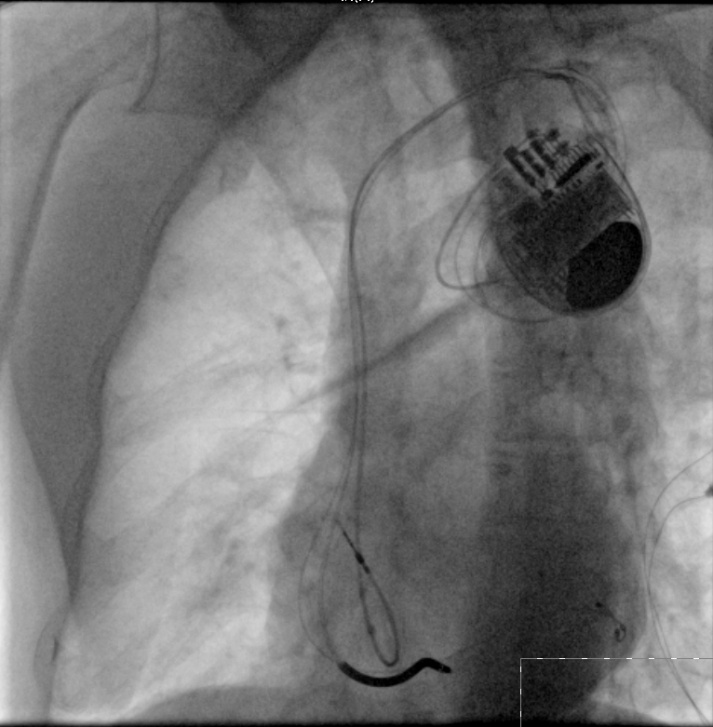

心衰中心的好處有多大?來看看這兩位——

帶除顫功能的三腔起搏器植入術(shù)(CRTD)